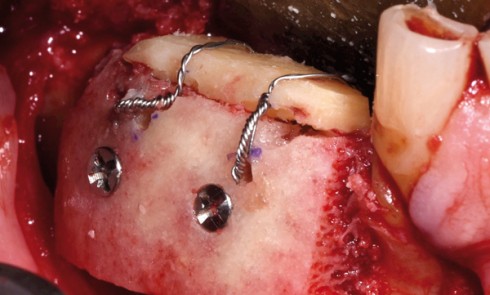

Allogreffes et reconstructions de crête à but préimplantaire Nous avons étudié 100 greffes d’origine allogénique à but préimplantaire réalisées au...

Dans cet article, nous nous intéressons aux indications des allogreffes en chirurgie buccale, en particulier après l’exérèse de kystes des...

Article réservé à nos abonnés Utilisation systématique de greffes allogéniques selon un protocole spécifique

Malgré les prouesses technologiques réalisées par les industriels pour proposer des implants toujours plus courts ou plus étroits, dans le...